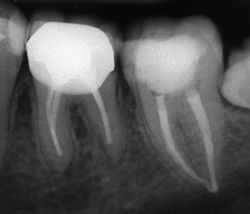

Ендодонтията е раздел от съвременната дентална медицина, който раздел изучава физиологията и патологията на вътрешната част на зъба - пулпна кухина и коренови канали. Названието на раздела идва от старогръцки - ендос - представка за вътрешност и одонтос - зъб. Това е една от научните дисциплини, които претърпяха голямо развитие през последното деситилетие.